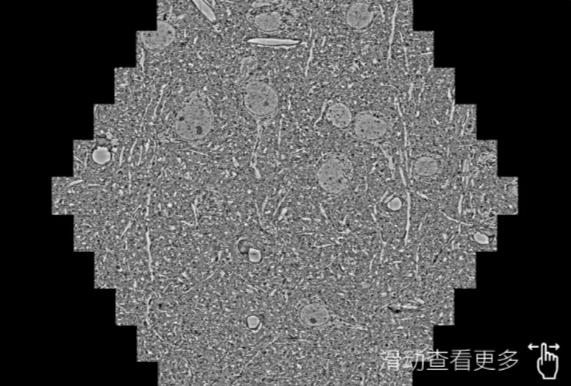

鼠脑切片。左图使用晋中蔡司晋中扫描电镜MultiSEM706对165μmx143pm面积区域成像,耗时仅需1.5秒。右图为鼠脑切片中30μm区域放大效果。样品由芝加哥大学B.Kasthuri提供。

使用蔡司高速晋中扫描电镜MultiSEM对1mm²人脑皮层组织进行高分辨成像,并对其中的各种细胞结构进行三维重构分析。左图展示了2x3mm²组织平面中锥体神经元的三维重构效果。右图显示了局部体积神经元三维重构。图像由哈佛大学chtman实验室提供,渲染图由D. Berger 制作。